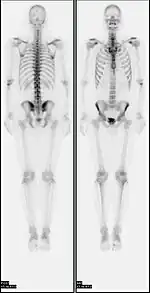

A nuclear medicine whole body bone scan. The nuclear medicine whole body bone scan is generally used in evaluations of various bone-related pathology, such as for bone pain, stress fracture, nonmalignant bone lesions, bone infections, or the spread of cancer to the bone.